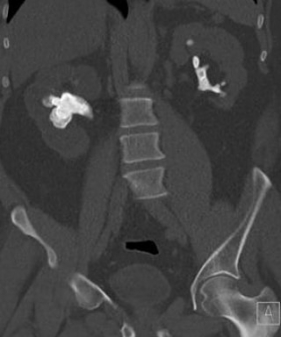

Cuatro imágenes de cálculos renales coraliformes.